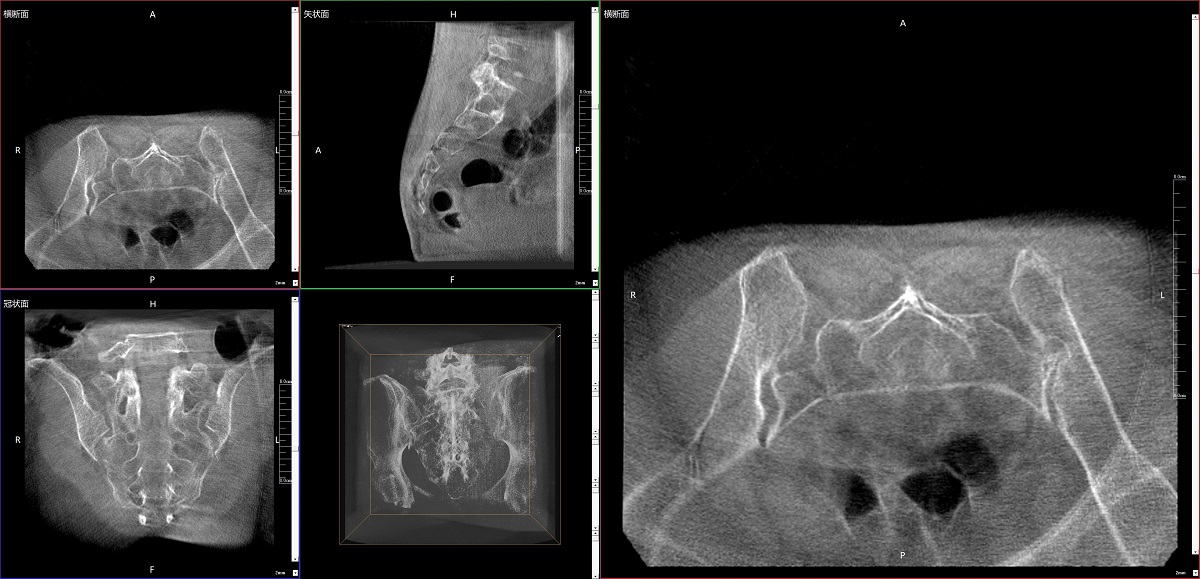

在骨科手術(shù)中,影像相當(dāng)于醫(yī)生的“眼睛”,要先“看得清",才能“算得準(zhǔn)” “打得穩(wěn)”。普愛醫(yī)療第三代平板三維C形臂協(xié)同醫(yī)院創(chuàng)傷導(dǎo)航機(jī)器人已開展多例“骨盆骨折微創(chuàng)手術(shù)”,成為上海市第七人民醫(yī)院手術(shù)技術(shù)創(chuàng)新的一大亮點(diǎn)。

普愛醫(yī)療第三代平板三維C形臂出色的二維透視和術(shù)中三維成像效果,為機(jī)器人提供了精確的術(shù)中影像依據(jù),協(xié)同提升手術(shù)整體的精準(zhǔn)度和效率,為患者帶來了更安全、更高效的醫(yī)療服務(wù)體驗(yàn)。